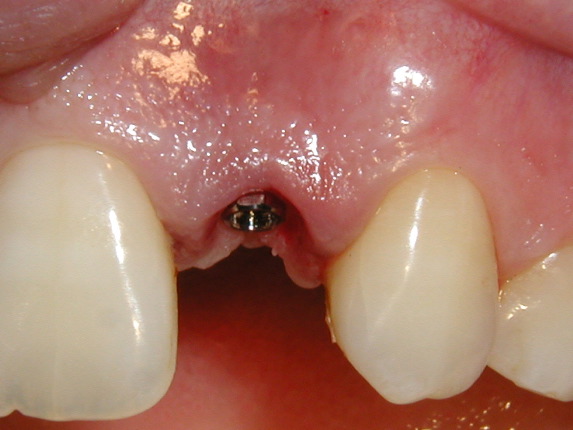

| Missing tooth | Implant placed |

This procedure allows the placement of an implant with a temporary crown on the same day with no need for sutures. There is so little discomfort that most patients go back to work and use only mild "over the counte" type medications.